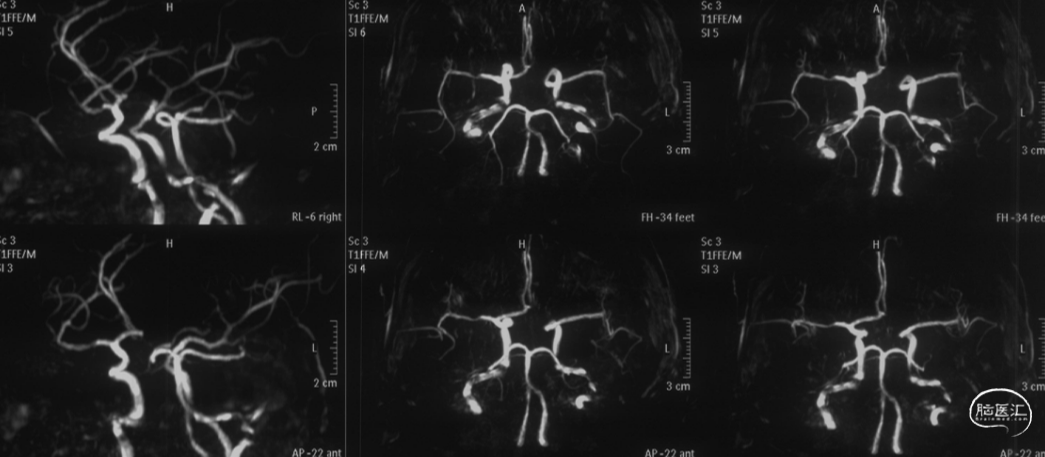

MRV可见上矢状窦及右侧横窦充盈缺损。

术前DSA静脉期可见上矢状窦及右侧横乙窦充盈缺损。